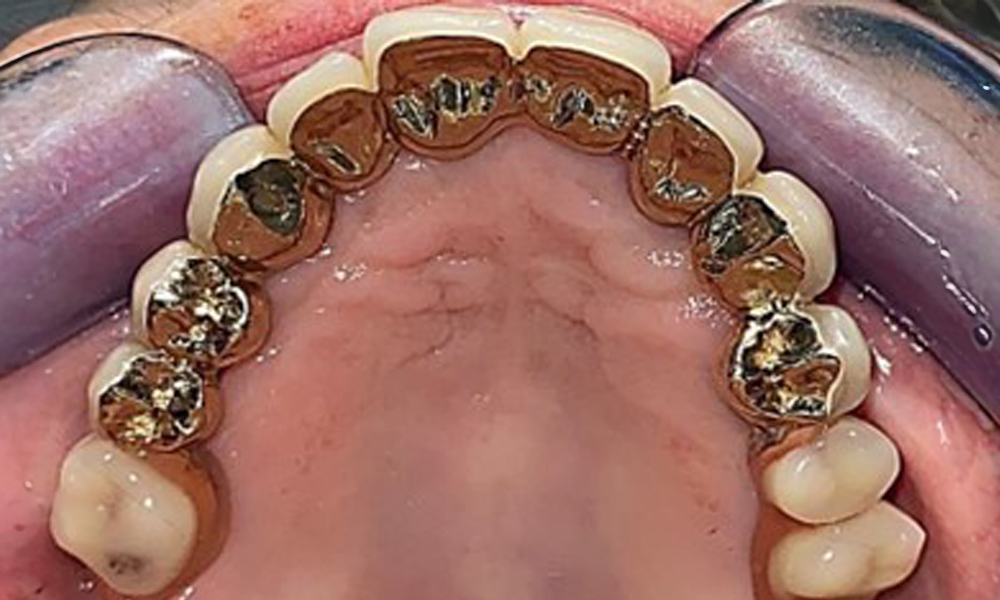

The patient was fitted with a combined removable maxillary telescopic prosthesis more than 25 years ago (Fig. 1, Fig. 2, Fig. 3) and is very happy with her dentures. The patient has an adequate fixed denture for the mandible (Fig. 4).

The dental findings are as follows: Combined removable implant and tooth-supported telescopic prostheses on implants 15, 13, 21, 23, 24, 25 and tooth 11 (Fig. 1, Fig. 2, Fig. 3). The patient was fitted with a fixed mandibular denture. Adequate bridges were present over 37 to 34 and 45 to 47 (Fig. 4), the crown margins were intact and there were no active caries. A composite filling with a marginal gap was present on tooth 43. There was mandibular gingival recession, exposing 1 to 3 mm of root surface. This also applies to 11.

The intraoral mucosa must be examined for possible fungal infections and pressure spots. The dentures must be visually inspected for cleanliness. The present case presented with interdental discolouration, attributed to tea consumption (Fig. 7). The dentures should be professionally cleaned in the dental practice using disinfection and cleaning baths.